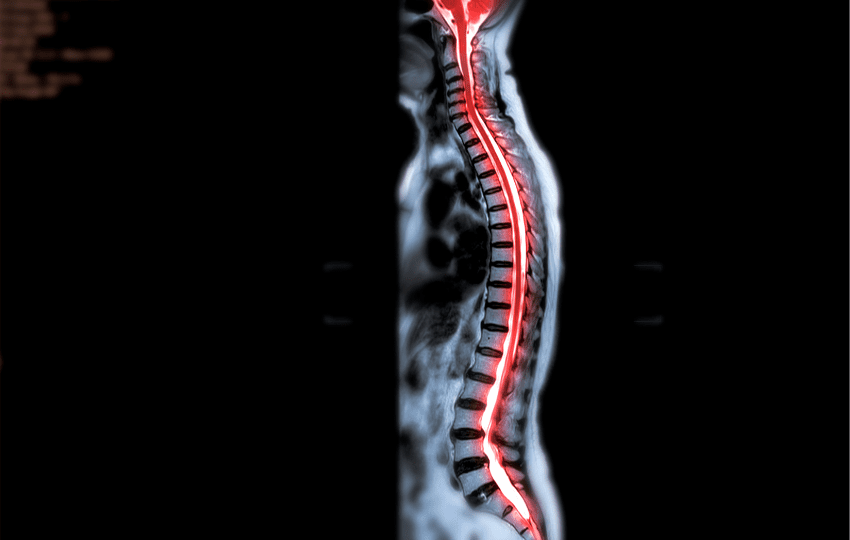

O choque neurogênico ocorre principalmente como consequência de lesão aguda da medula espinhal, especialmente em níveis cervicais ou torácicos altos. É mais comum em lesões nas vértebras cervicais e torácicas superiores, acima do nível de T6.

O choque neurogênico é um tipo de choque distributivo que ocorre principalmente após lesão medular aguda, especialmente em lesões cervicais ou torácicas altas. Caracteriza-se por hipotensão arterial associada a bradicardia, resultantes da perda do tônus simpático devido à interrupção das vias autonômicas da medula espinhal.